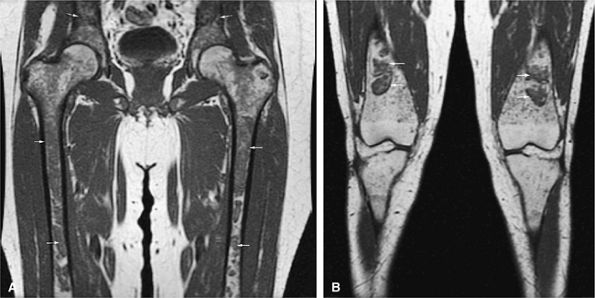

FIGURE 13.73 ● Accumulation of lipid in reticuloendothelial cells in Gaucher disease. Patchy low-signal-intensity marrow infiltration (arrows) can be seen on a coronal T1-weighted image of the pelvis and proximal femurs (A) and on a coronal T1-weighted image of the knees (B). There may be relative sparing of the epiphyses and apophyses until later stages of disease.

FIGURE 13.74 ● Gaucher disease involving the appendicular skeleton. Low-signal marrow infiltration is noted on a coronal image of the femurs (A) and lower legs (B). Extension into the epiphysis and distal skeleton is characteristic of advanced disease.